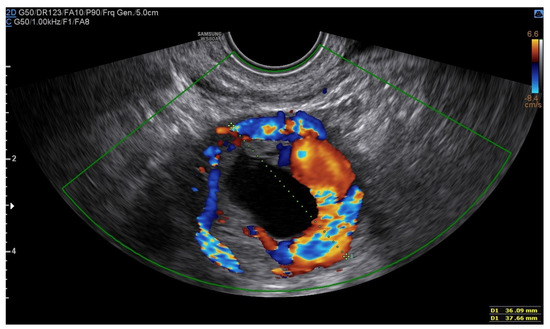

A 25-year-old woman, with a history of left tubal laparoscopic salpingectomy for an ectopic pregnancy, sought medical attention at the hospital’s emergency department after an episode of vaginal bleeding at 5 + 6 weeks of amenorrhea. At Day-1, her β-hCG was 2528 mUI/mL but a transvaginal ultrasound scan (TVUS) showed no clear evidence of pregnancy. Therefore, the patient was admitted with a diagnosis of pregnancy of unknown location (PUL). Upon admission, the patient was clinically and hemodynamically stable and did not report any pain or active bleeding. Serial measurement of her β-hCG in the following days was consistent with a suboptimal growth (3696 at Day-2, 5898 at Day-4, 10,984 at Day-7). Repeated TVUSs failed to show sure evidence of pregnancy until Day-7, when an intramural vascularized mass of 27 × 8 × 20 mm, with a gestational sac of 7 mm, a yolk sac and a 2 mm embryo with a heartbeat, was detected (Figure 1). Pelvic nuclear magnetic resonance (NMR) performed at Day-7 confirmed the presence of an intramyometrial T2-hypointense signal alteration of 20 mm in the right cornual area, surrounded by ectasic vessels, suggestive of interstitial pregnancy (Figure 2). After thorough counselling, a conservative management was proposed and accepted by the patient. The patient was administered a single oral dose of mifepristone 600 mg in combination with multidose systemic MTX 72 mg on days 0, 2, 4 and 6 from diagnosis. Follow-up by TVUS and β-hCG measurement was carried out. By Day-15, β-hCG reached a plateau and started reducing. A TVUS confirmed the termination of the pregnancy by involution of the gestational sac and the presence of the embryo with the disappearance of the fetal heartbeat. After 22 days from treatment, while the pregnancy was disappearing, in the same site, TVUS showed the appearance of a myometrial tubular hypoechoic region of 37 × 38 mm with an intensely vascular and multidirectional flow. Spectral Doppler ultrasound showed a low-resistance, high-velocity (peak systolic velocity of 128 cm/s) flow pattern, suggestive of uterine arteriovenous malformation (AVM) in the location of the previous interstitial pregnancy (Figure 3). The patient remained asymptomatic. To avoid menstrual bleeding and minimize the risk of metrorrhagia, a depot 3.75 mg shot of a GnRH analogue was administered every 28 days for 4 months. Considering the desire to preserve the fertility of the patient, the absence of guidelines for the treatment of AVM and the good results presented in the literature on uterine artery embolization as a conservative treatment, we performed a right uterine artery embolization, with sonographic resolution of the AVM within 3 months (Figure 4). We accessed the right common femoral artery and a 5-Fr introducing an angiographic sheath was placed. A 5-Fr Cobra catheter (Cook, Bloomington, IN, USA) was used to perform nonselective angiograms of the internal iliac arteries in order to achieve a general understanding of the vascular anatomy; the right internal iliac artery was selected after creating a Waltman loop with the Cobra catheter. The right uterine artery was selected using a microcatheter ranging from 2.0 to 2.4 Fr. As embolic materials, polyvinyl alcohol particles were used (Contour; Boston Scientific, Cork, Ireland). The rescue treatment had no complications. We present an unpublished case of interstitial pregnancy in a hemodynamically stable woman at an early gestational age successfully treated with medical therapy using MTX and mifepristone, who developed a peculiar complication.

Figure 1. The green line identifies the gestational sac and a 2 mm embryo without a heartbeat.